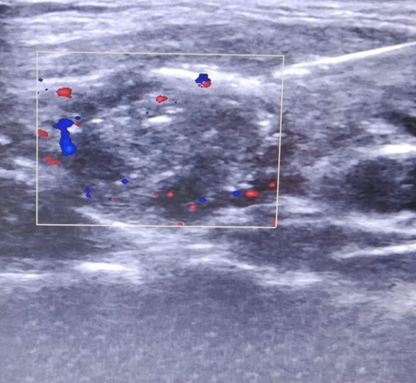

按照病理可以分为结节性甲状腺肿、甲状腺腺瘤、甲状腺炎、甲状腺癌等。发现甲状腺结节最简单有效而且便宜的方法就是甲状腺彩超。彩超对甲状腺结节的敏感性非常高,大于1厘米的结节都无处遁形。

TI-RADS 5类(表现为等或低回声结节,无明显包膜,伴有多发微小钙化灶,结节内血流丰富)结节和TI-RADS 6类(包括活检证实恶性和规则或不规则极低回声结节,无包膜,边缘不规整,呈毛刺状或边界不清或呈浸润性生长,伴有微小钙化灶,结节血流丰富)结节,则需要尽快行手术治疗,利用术中快速冰冻病理检查明确诊断行根治性手术治疗。